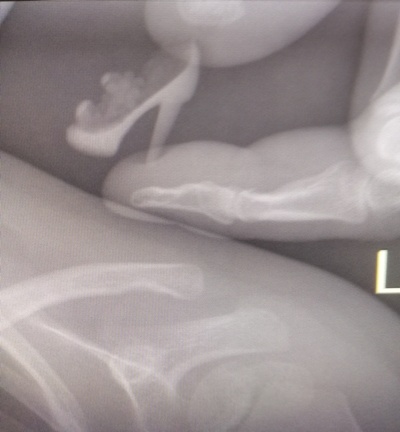

Подозрение на инородное тело желудочно-кишечного тракта.

При выполнении обзорной рентгенограммы органов грудной клетки, брюшной полости и забрюшинного пространства в проекции желудка определяется включение средней интенсивности, неоднородной структуры, неправильной формы.

При внимательном изучении рентгенологического снимка становится ясно, что инородное тело не что иное, как...

... туфелька её куклы!!